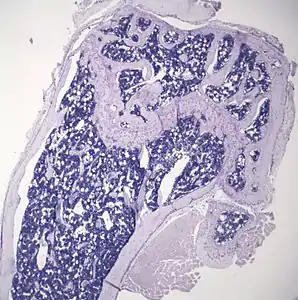

- Histologic sections demonstrating Marrow Adipocytes

Representative distal femur histologic section of a 16-week-old healthy C57BL/6 mouse demonstrating a typical quantity of marrow adipocytes.